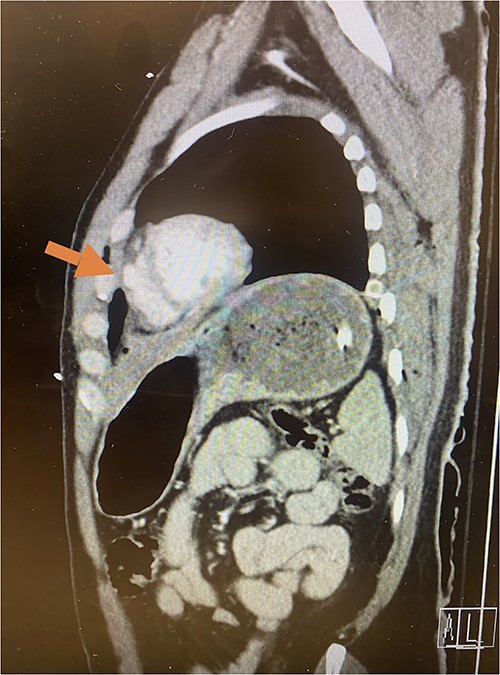

Given his hemodynamic normalization without ongoing transfusion requirements, he was taken to the computed tomography (CT) scanner for axial imaging of the head, chest, abdomen and pelvis. A CT angiogram of the chest revealed trace pneumopericardium and pneumomediastinum with trace hemopericardium. A 1.7 × 0.7 cm out-pouching at the anterior aspect of the right ventricular apex concerning for a traumatic pseudoaneurysm was also detected (see Figs 2 and 3). His other injuries were notable for subarachnoid and subdural hemorrhages, left temporal bone fracture, open mandibular fracture, left 3–6th, 10th and 11th rib fractures, a 4th lumbar vertebrae burst fracture with 1st and 3rd lumbar vertebrae compression fractures, 8–11th thoracic vertebrae compression fractures, and a left femoral neck fracture. He was subsequently transferred back to the trauma bay where a formal trans-thoracic echocardiogram was immediately performed, which demonstrated a dyskinetic area of the right ventricular apex with paradoxical out-pouching during systole—suggestive of pseudoaneurysm and confirming the diagnosis on axial imaging.

Axial CT imaging demonstrating pseudoaneurysm of right ventricular free wall rupture.

Sagittal CT imaging demonstrating pseudoaneurysm of right ventricular free wall rupture.